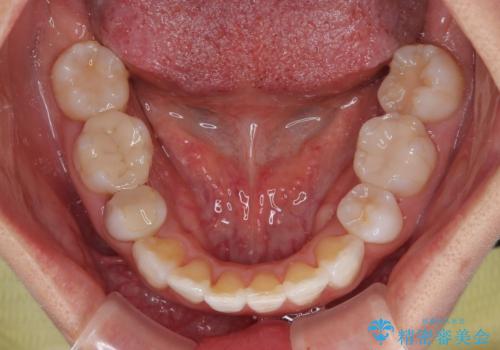

- 上下前歯の後戻りを気にして来院された患者様です。

インビザラインでの治療を希望されていて、デコボコの程度が中等度であり、安価なパッケージにて対応可能と判断されたため、インビザライン・モデレートを用いて矯正治療を行うこととしました。

インビザライン・モデレートは、製作できるアライナーの枚数に制限があるため、移動可能な量に限りがあるものの、インビザライン・ライトよりも枚数が多いため、幅広い症例に対応可能です。